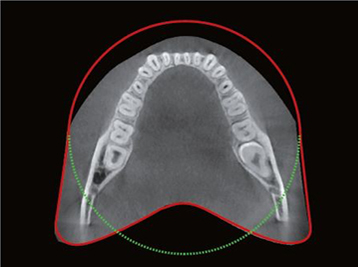

Анатомическое поле сканирования

Передовая технология захвата арочного пространства зубной дуги обеспечивает съемку более обширной области по сравнению с обычными аппаратами, имеющими поле зрения 10×8,5. Это позволяет получить изображение 8 зубов без риска повреждения корней, даже если третьи моляры находятся в ретенированном состоянии.